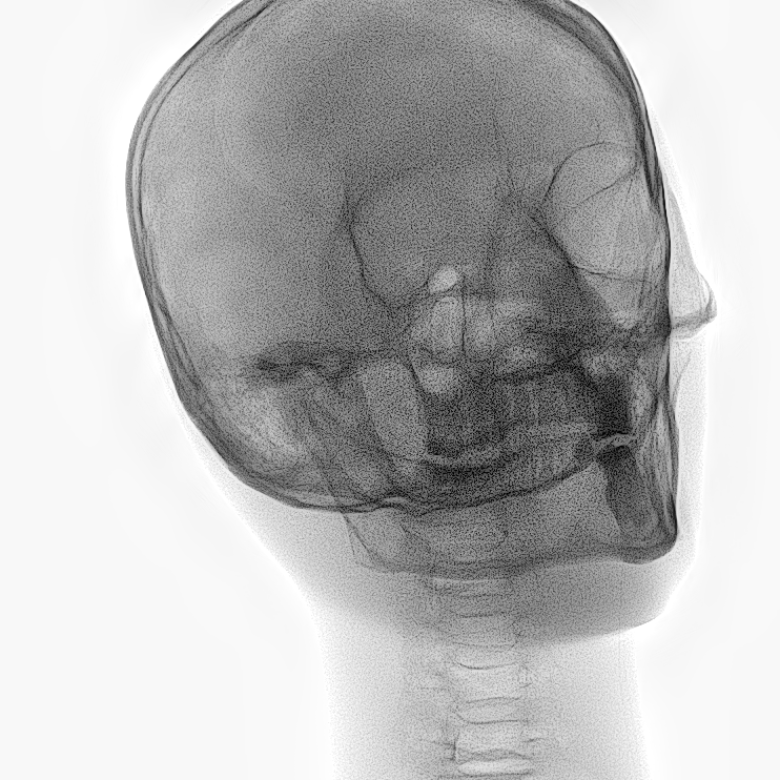

Refer to caption

Figure 2: Dataset overview. The synthetic domain contains Low and High dosage samples generated using the Mentice VIST® simulator; the real domain includes Low, Normal, and Exposure dosage categories acquired from a skull phantom using the Philips Azurion IGT system.

We develop and release a new dataset of real and synthetic head X-ray images, X-DigiSkull, to study the domain adaptation. The dataset consists of synthetic X-ray images of a human skull generated using the Mentice VIST® simulator 111https://www.mentice.com/simulator/vist-g7. Real‑time X‑rays are generated by holding the 3D voxel “patient” head model with per‑voxel attenuation, casting one ray per detector pixel to form a digitally reconstructed radiograph and then approximating scatter, focal‑spot and detector blur, grid/heel effects and detector response, adding quantum/read noise and final image post-processing as the C‑arm and devices move. Real images are acquired from a clinical-grade physical skull phantom using the Philips Azurion Image Guided Therapy (IGT) system. Images are captured from common IGT working positions for neuro procedures. The dataset consists of multiple orientations and is available in three different radiation dose settings: low, normal, and exposure (Philips exclusive), the latter offering enhanced image quality and detail, as shown in Figure 2. This consists of viewing angles rz[40,+40]r_{z}\in[-40^{\circ},+40^{\circ}], ry[40,+40]r_{y}\in[-40^{\circ},+40^{\circ}], rx[40,+40]r_{x}\in[-40^{\circ},+40^{\circ}] with respect to the starting position in 10 increments and up to 3 images at each position to capture the noise present. This results in a total of 2,187 real images. The coordinate systems of the real and synthetic environment are aligned and synthetic images are rendered to approximate the same viewpoints as the real phantom images with the patient table starting at a similar position.The head 3D model used in the simulation is meticulously built from a real clinical case. We capture the synthetic images in finer increments of 5 across the three angles, producing the 5,832 (18318^{3}) images 222Data available at https://zenodo.org/records/16535437. The aim of this alignment is not to achieve precise supervised image translation, but rather to establish a consistent reference structure that preserves spatial features. The composition of the dataset is summarized in Table 1, which contains information on the splits and the number of images available. All images are cropped and resized to 780×\times780 pixels. The test set is obtained by uniformly sampling 15% of viewing angles and corresponding images to ensure a representative distribution. For our experiments, we focus on the task of converting synthetic images at high dose to real images at normal dose.